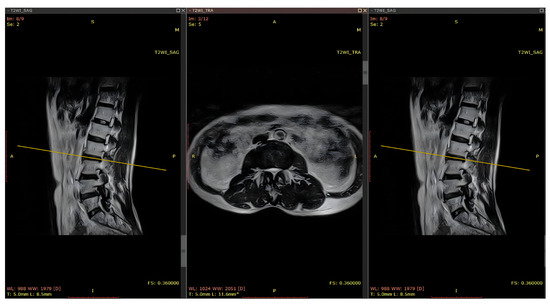

4.1. Spine Dataset

The spinal data for this experiment come from the “Alibaba Cloud Tianchi Algorithm Competition “Spark” Digital Human AI Challenge-Intelligent Diagnosis of Spine Diseases”, which is provided by Wanli Cloud and AllinMD Orthopaedics. It provides T1 and T2 sagittal images of the spine and T2 axial position (FSE/ TSE) images, and the picture format is DCM. Figure 3 displays example plots of T1-weighted sagittal, T2-weighted sagittal, and T1-weighted axial images in the dataset. We chose T2-weighted imaging for training our model primarily for its high efficacy in depicting edema and inflammation around intervertebral discs, which enhances the identification and classification of pathological features. During the detailed classification phase, composite images that merged both axial and sagittal views were exclusively created using T2-weighted imaging. This ensured uniformity in imaging technique across the merged views, optimizing our model’s learning process.

Figure 3. The example types of images in the dataset provided by Tianchi competition. (Left) T2-weighted sagittal image. (Middle) T2-weighted axial image. (Right) T1-weighted sagittal image. T1-weighted images are produced by using short TE and TR times, while T2-weighted images are produced by using longer TE and TR times.